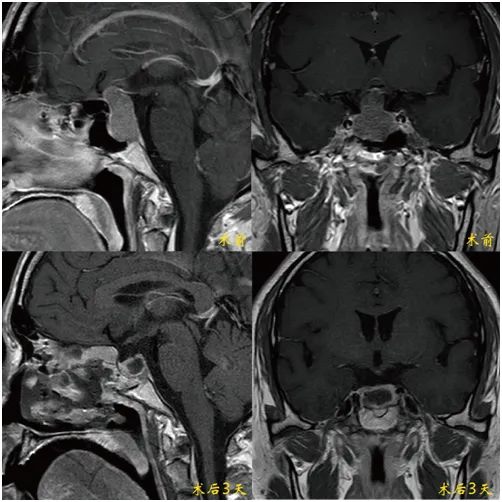

"眼前突然模糊的那一刻,我知道这不是疲劳。"作为河南省某三甲医院外科主任,刘主任(化名)在连续完成多台高难度手术后,敏锐察觉到自己双眼视野缺损。头颅MRI检查结果令人心惊:鞍区赫然盘踞着直径3.5cm的巨大垂体腺瘤,视交叉结构已被严重挤压变形。

"3厘米以上的垂体瘤即可定义为巨大肿瘤,而视交叉受压超过3个月将造成不可逆损伤。"郑州大学第五附属医院神经外科一病区主刀专家寿记新主任解释。这位常年拯救患者的医者,此刻比任何人都清楚——这是一场与时间的赛跑。

20ml微量出血:完美避开颈内动脉与海绵窦出血风险

120分钟内:完整切除肿瘤

真正微创:经鼻蝶入路实现

术后次日,刘主任手持视力表的声音有些颤抖。这位资深专家从专业视角给出震撼评价:"作为同行更能体会这台手术的含金量,从内镜入路角度的选择到肿瘤包膜的处理,每个细节都彰显着寿主任团队深厚的解剖功底和精湛的手术技艺。"